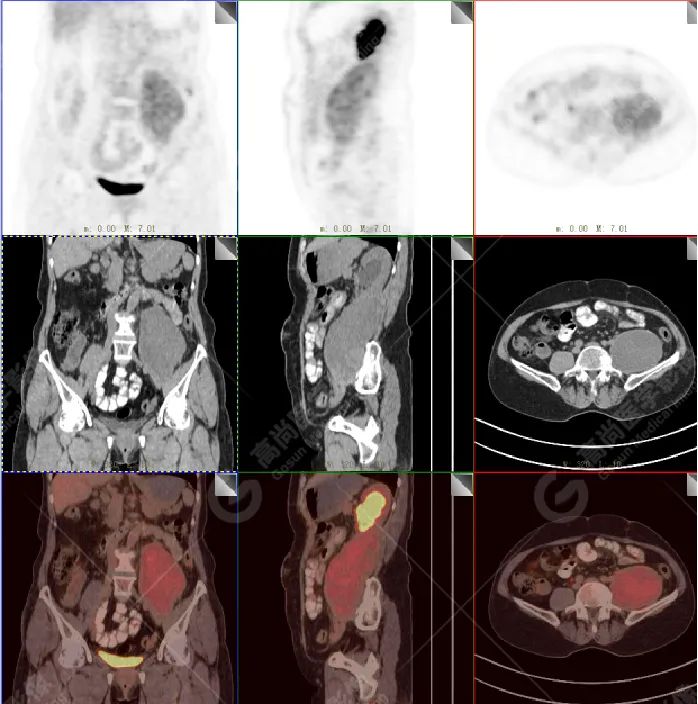

影像所见:左腹膜后间隙(原术区)见一长椭圆形软组织密度肿块影,范围约 8.0 cm×6.6 cm×15.8 cm,CT 值 30 Hu,FDG 高摄取,SUVmax5.0,考虑肿瘤复发,侵犯相邻左侧输尿管、腰大肌、后腹壁。

盆腔内(直肠右旁)见一转移性淋巴结,FDG 高摄取,SUVmax7.7。

增强扫描肿瘤不均性中度强化,动、静脉期 CT 值:41 Hu、72 Hu(平扫 CT 值 30 Hu)。

PET 表现:FDG 高摄取。